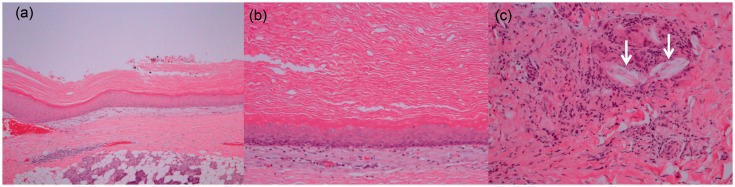

A 34-year-old man found a mildly tender preauricular mass. Ultrasonography revealed an anechoic mass in the superficial lobe of the parotid gland. Magnetic resonance imaging showed thin ring-like contrast enhancement and homogenously high intensity on T2-weighted images. The mass was resected due to its rapid growth. The cystic lesion contained keratine-like material and a stratified squamous epithelium without granular layers, which was consistent with keratocystoma.